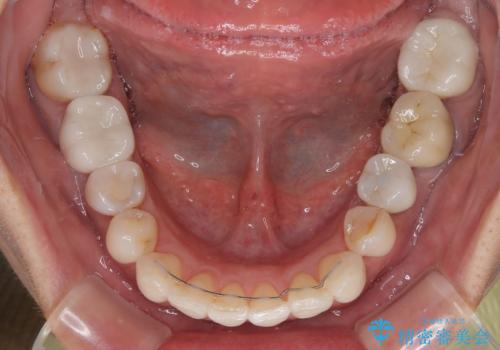

しっかりと装着時間を守ってくださり、来院のタイミングに合わせてインビザラインの装着期間を調整するなど、協力いただいたおかけで、1年半の期間で全てを終えることができました。

デコボコはある程度改善できれば良いとのことでしたので、インビザラインの廉価版を用いて矯正治療を行うこととしました。

飛行機での通院であり、更にはご家族がの都合で海外に滞在されることも多いため、中等度の歯列不正に対応可能なインビザライン・モデレートパッケージを使用することとしました。